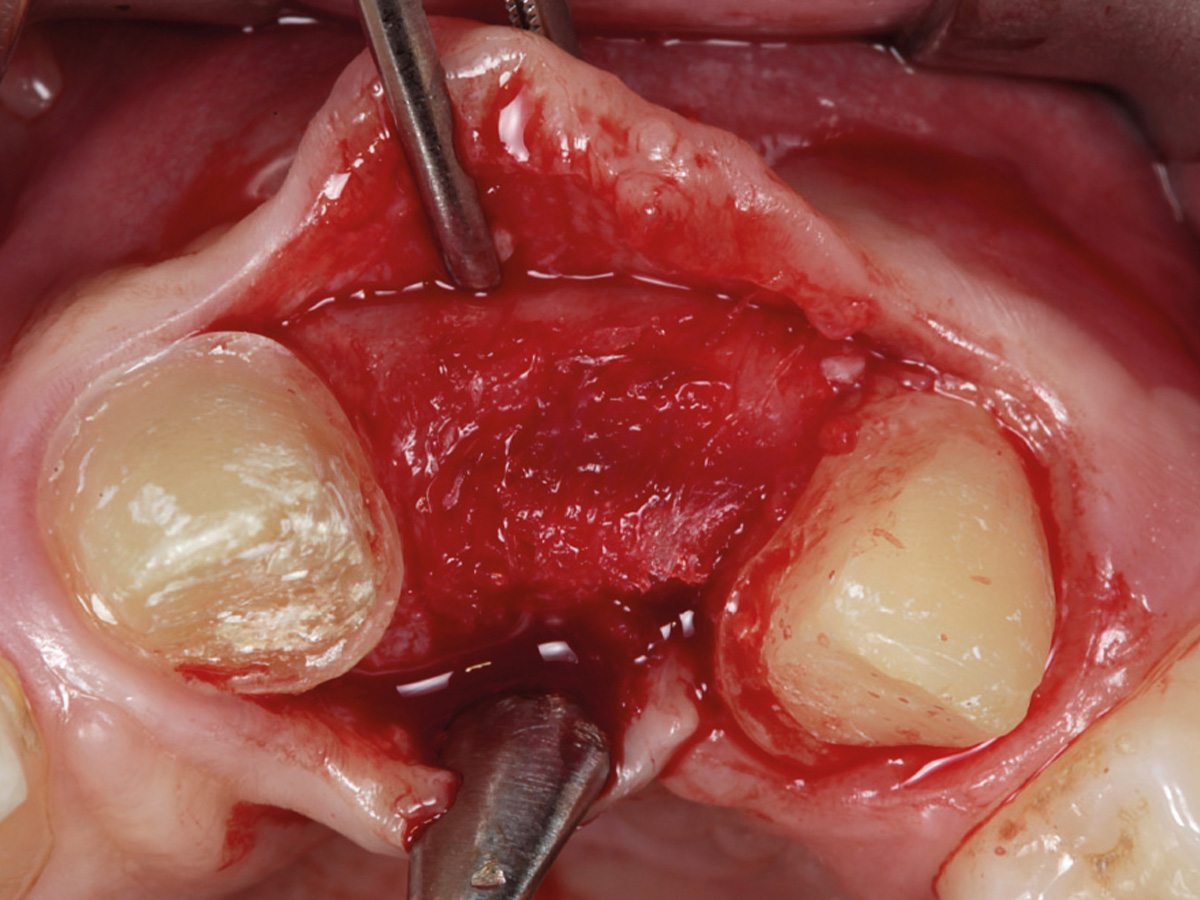

Abbildung 4

Der Defekt wird mit mp3® augmentiert.